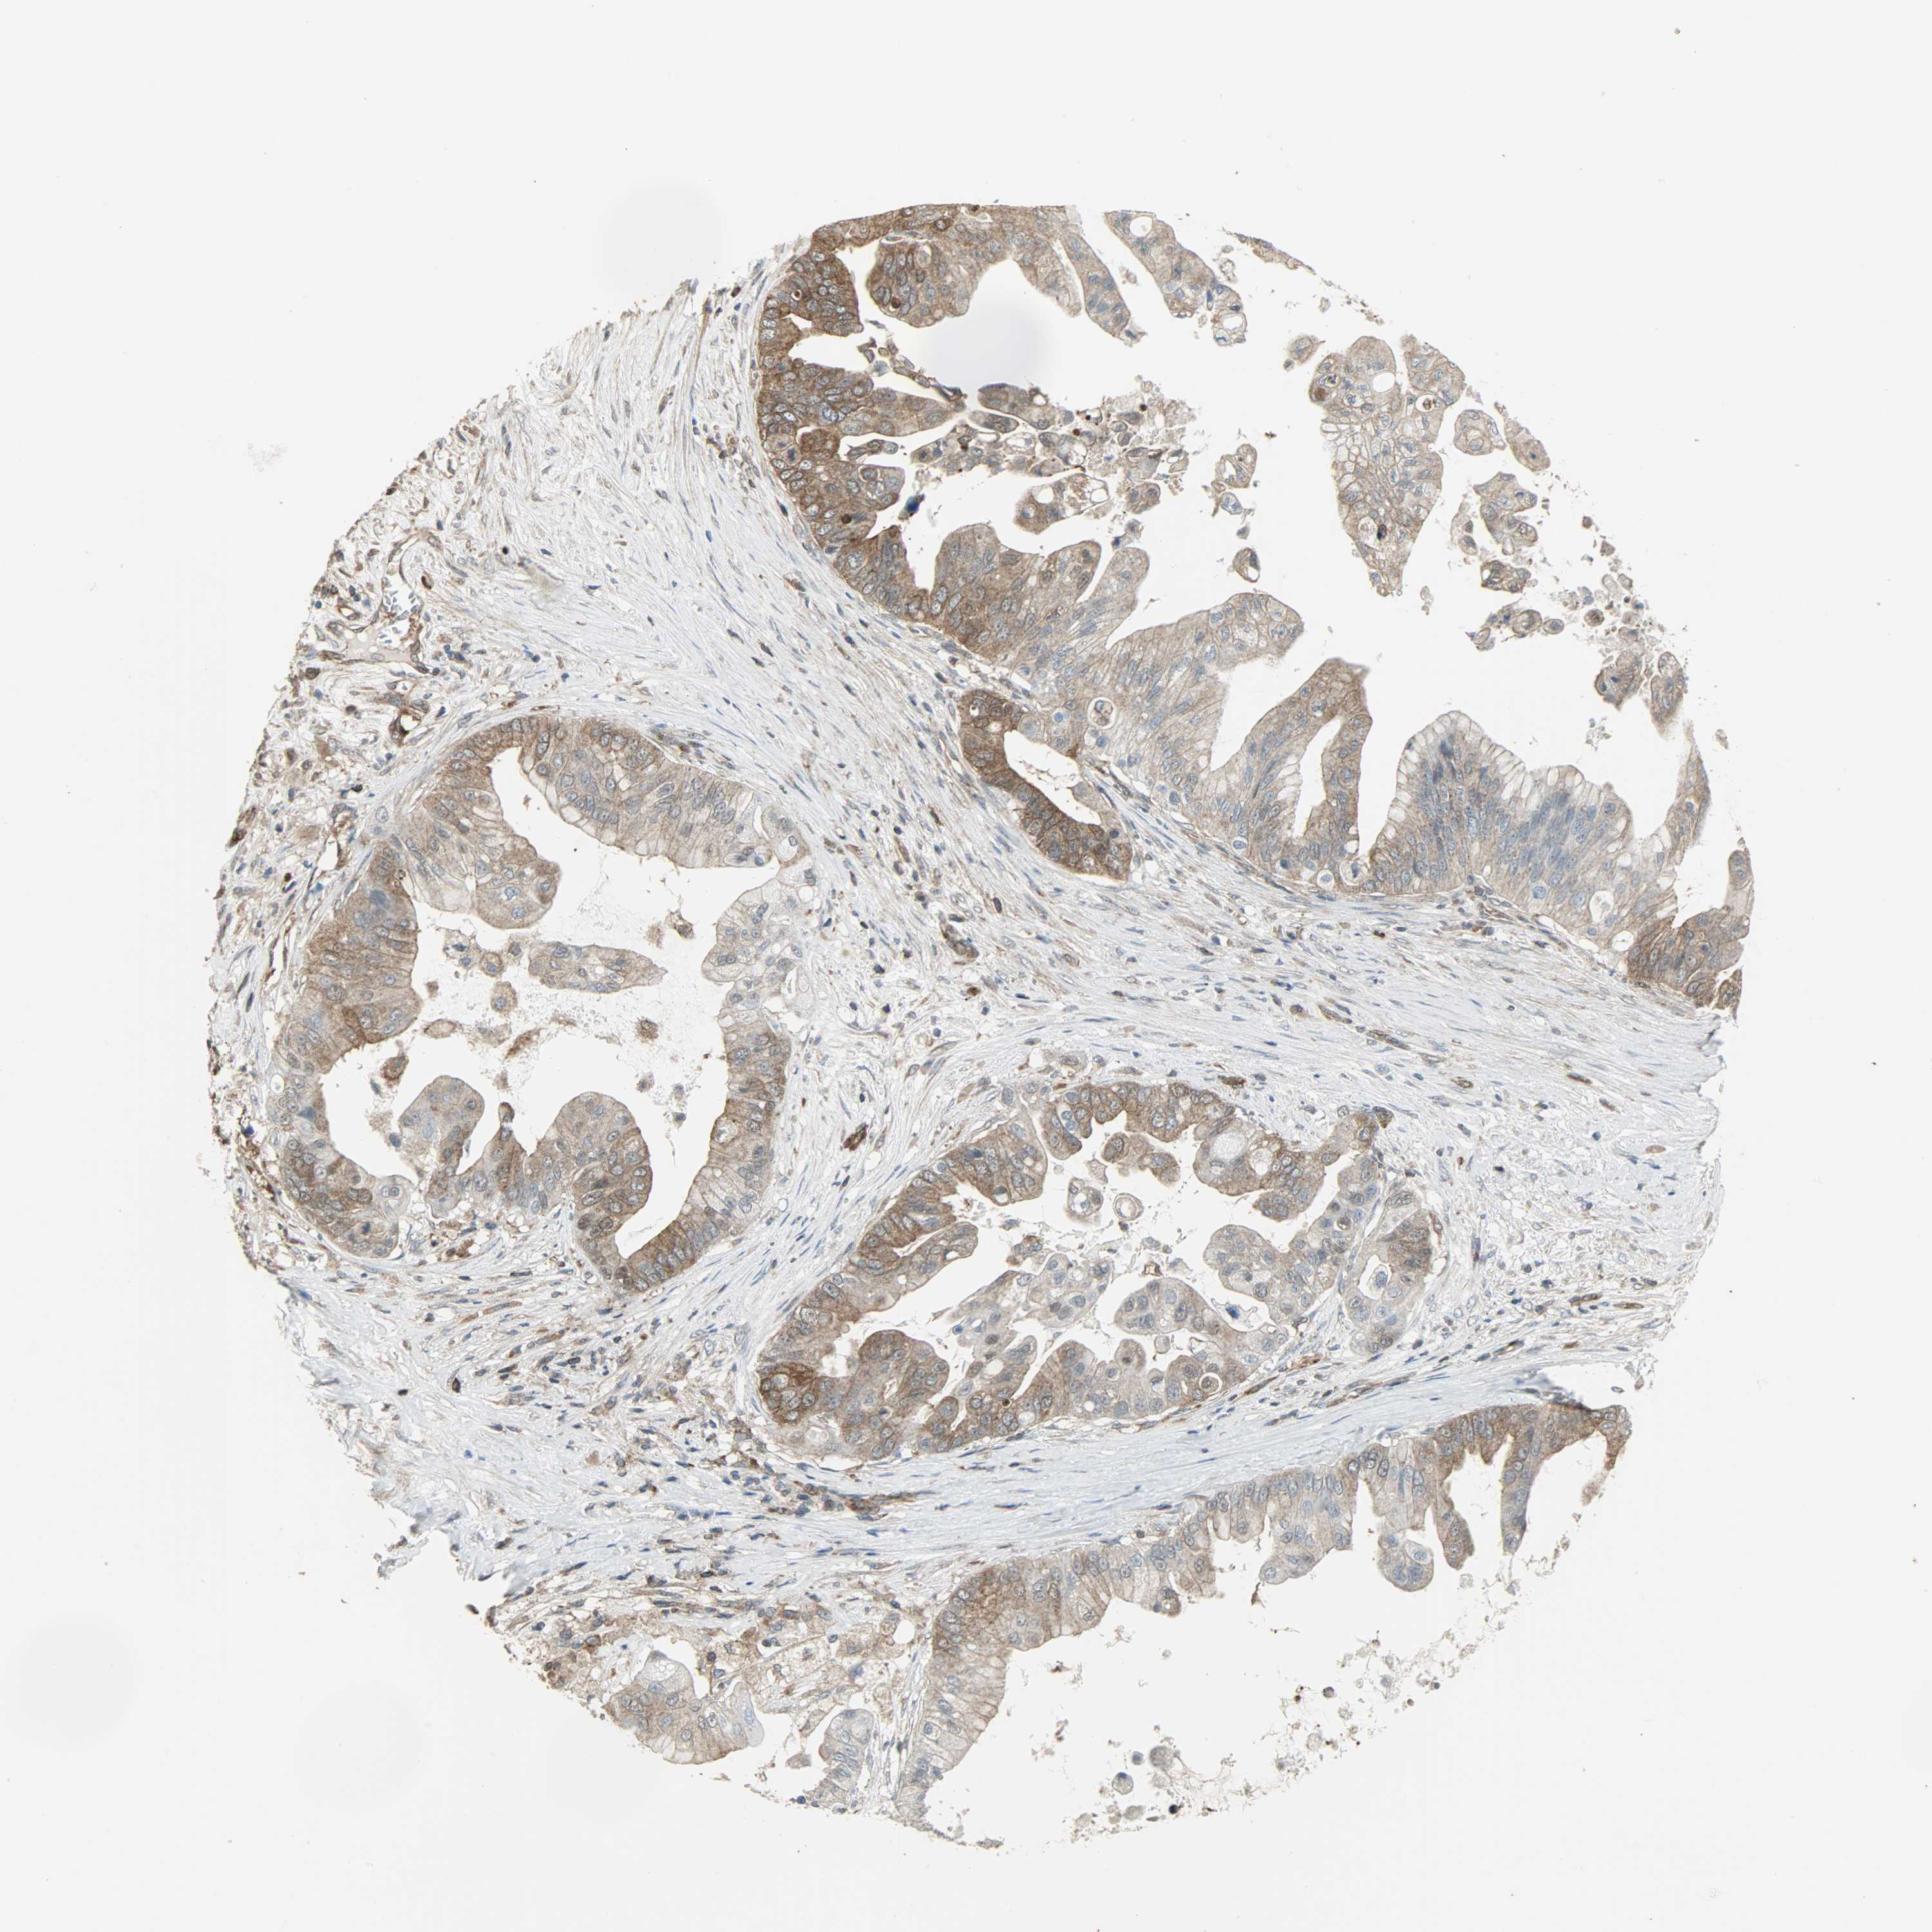

PANCREATIC CANCER - Protein expressioni

A mouse-over function shows sample information and annotation data. Click on an image to view it in a full screen mode. Samples can be filtered based on level of antibody staining by selecting one or several of the following categories: high, medium, low and not detected. The assay and annotation is described here.

Note that samples used for immunohistochemistry by the Human Protein Atlas do not correspond to samples in the TCGA dataset.

Antibody stainingi

Antibody staining in the annotated cell types in the current human tissue is reported as not detected, low, medium, or high, based on conventional immunohistochemistry profiling in selected tissues. This score is based on the combination of the staining intensity and fraction of stained cells.

Each image is clickable and will lead to virtual microscopy that enables deeper exploration of all samples and also displays staining intensity scores, fraction scores and subcellular localization as well as patient and tissue information for each sample.

Antibody HPA019007

Antibody CAB004641

Adenocarcinoma, NOS

Adenocarcinoma, metastatic, NOS